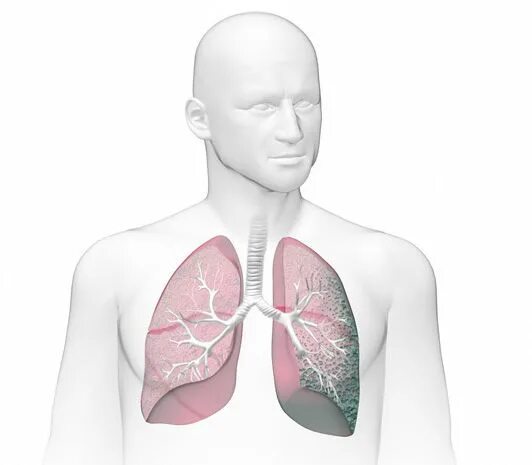

Как лечить пневмосклероз легких в пожилом возрасте